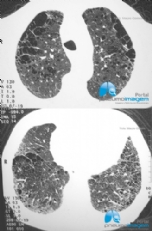

CASO CLÍNICO #56

Homem de 48 anos, tabagista e que se apresenta com dispneia. Qual o diagnóstico? Deixe seus comentários abaixo. *** A 48-year-old male smoker with dyspnoea. What is the diagnosis? Write your comments below.